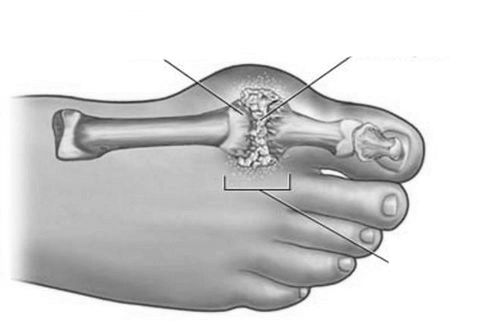

Остеоартроз також може викликати запалення суглоба великого пальця ноги. Це серйозне захворювання, яке часто призводить до повного руйнування суглоба. Це відбувається за рахунок того, що в хворому суглобі розростається сполучна тканина і перешкоджає його нормальному руху. Запалитися може і суглоб у другому великому пальці, тобто на іншій нозі.

Крім того, проводиться рентгенографія, вона покаже, що відбувається в суглобі. При запущеній формі хвороби досвідчений лікар візуально і за допомогою пальпації зможе визначити діагноз. Крім того, хворому буде призначено загальний аналіз крові та сечі. За ним теж можна визначити картину запалення. При необхідності призначається проведення комп'ютерної томографії. Така процедура, як антроскопія дозволить вивчити особливості пошкодженого суглоба.

Якщо суглоб на пальці сильно деформований і консервативні методи лікування не принесли полегшення, то доцільно хірургічне втручання. Оскільки суглоб втратив здатність повноцінно виконувати свої функції, навантаження повністю переходить на інші частини стопи. Такий стан викликає запалення суглоба, і згодом може утворитися грижа хребта. Хірургічне лікування має 2 варіанти:

- При наявності такої можливості відновлюється рухливість суглоба.

- Зруйнований суглоб видаляється і натомість його встановлюється протез.